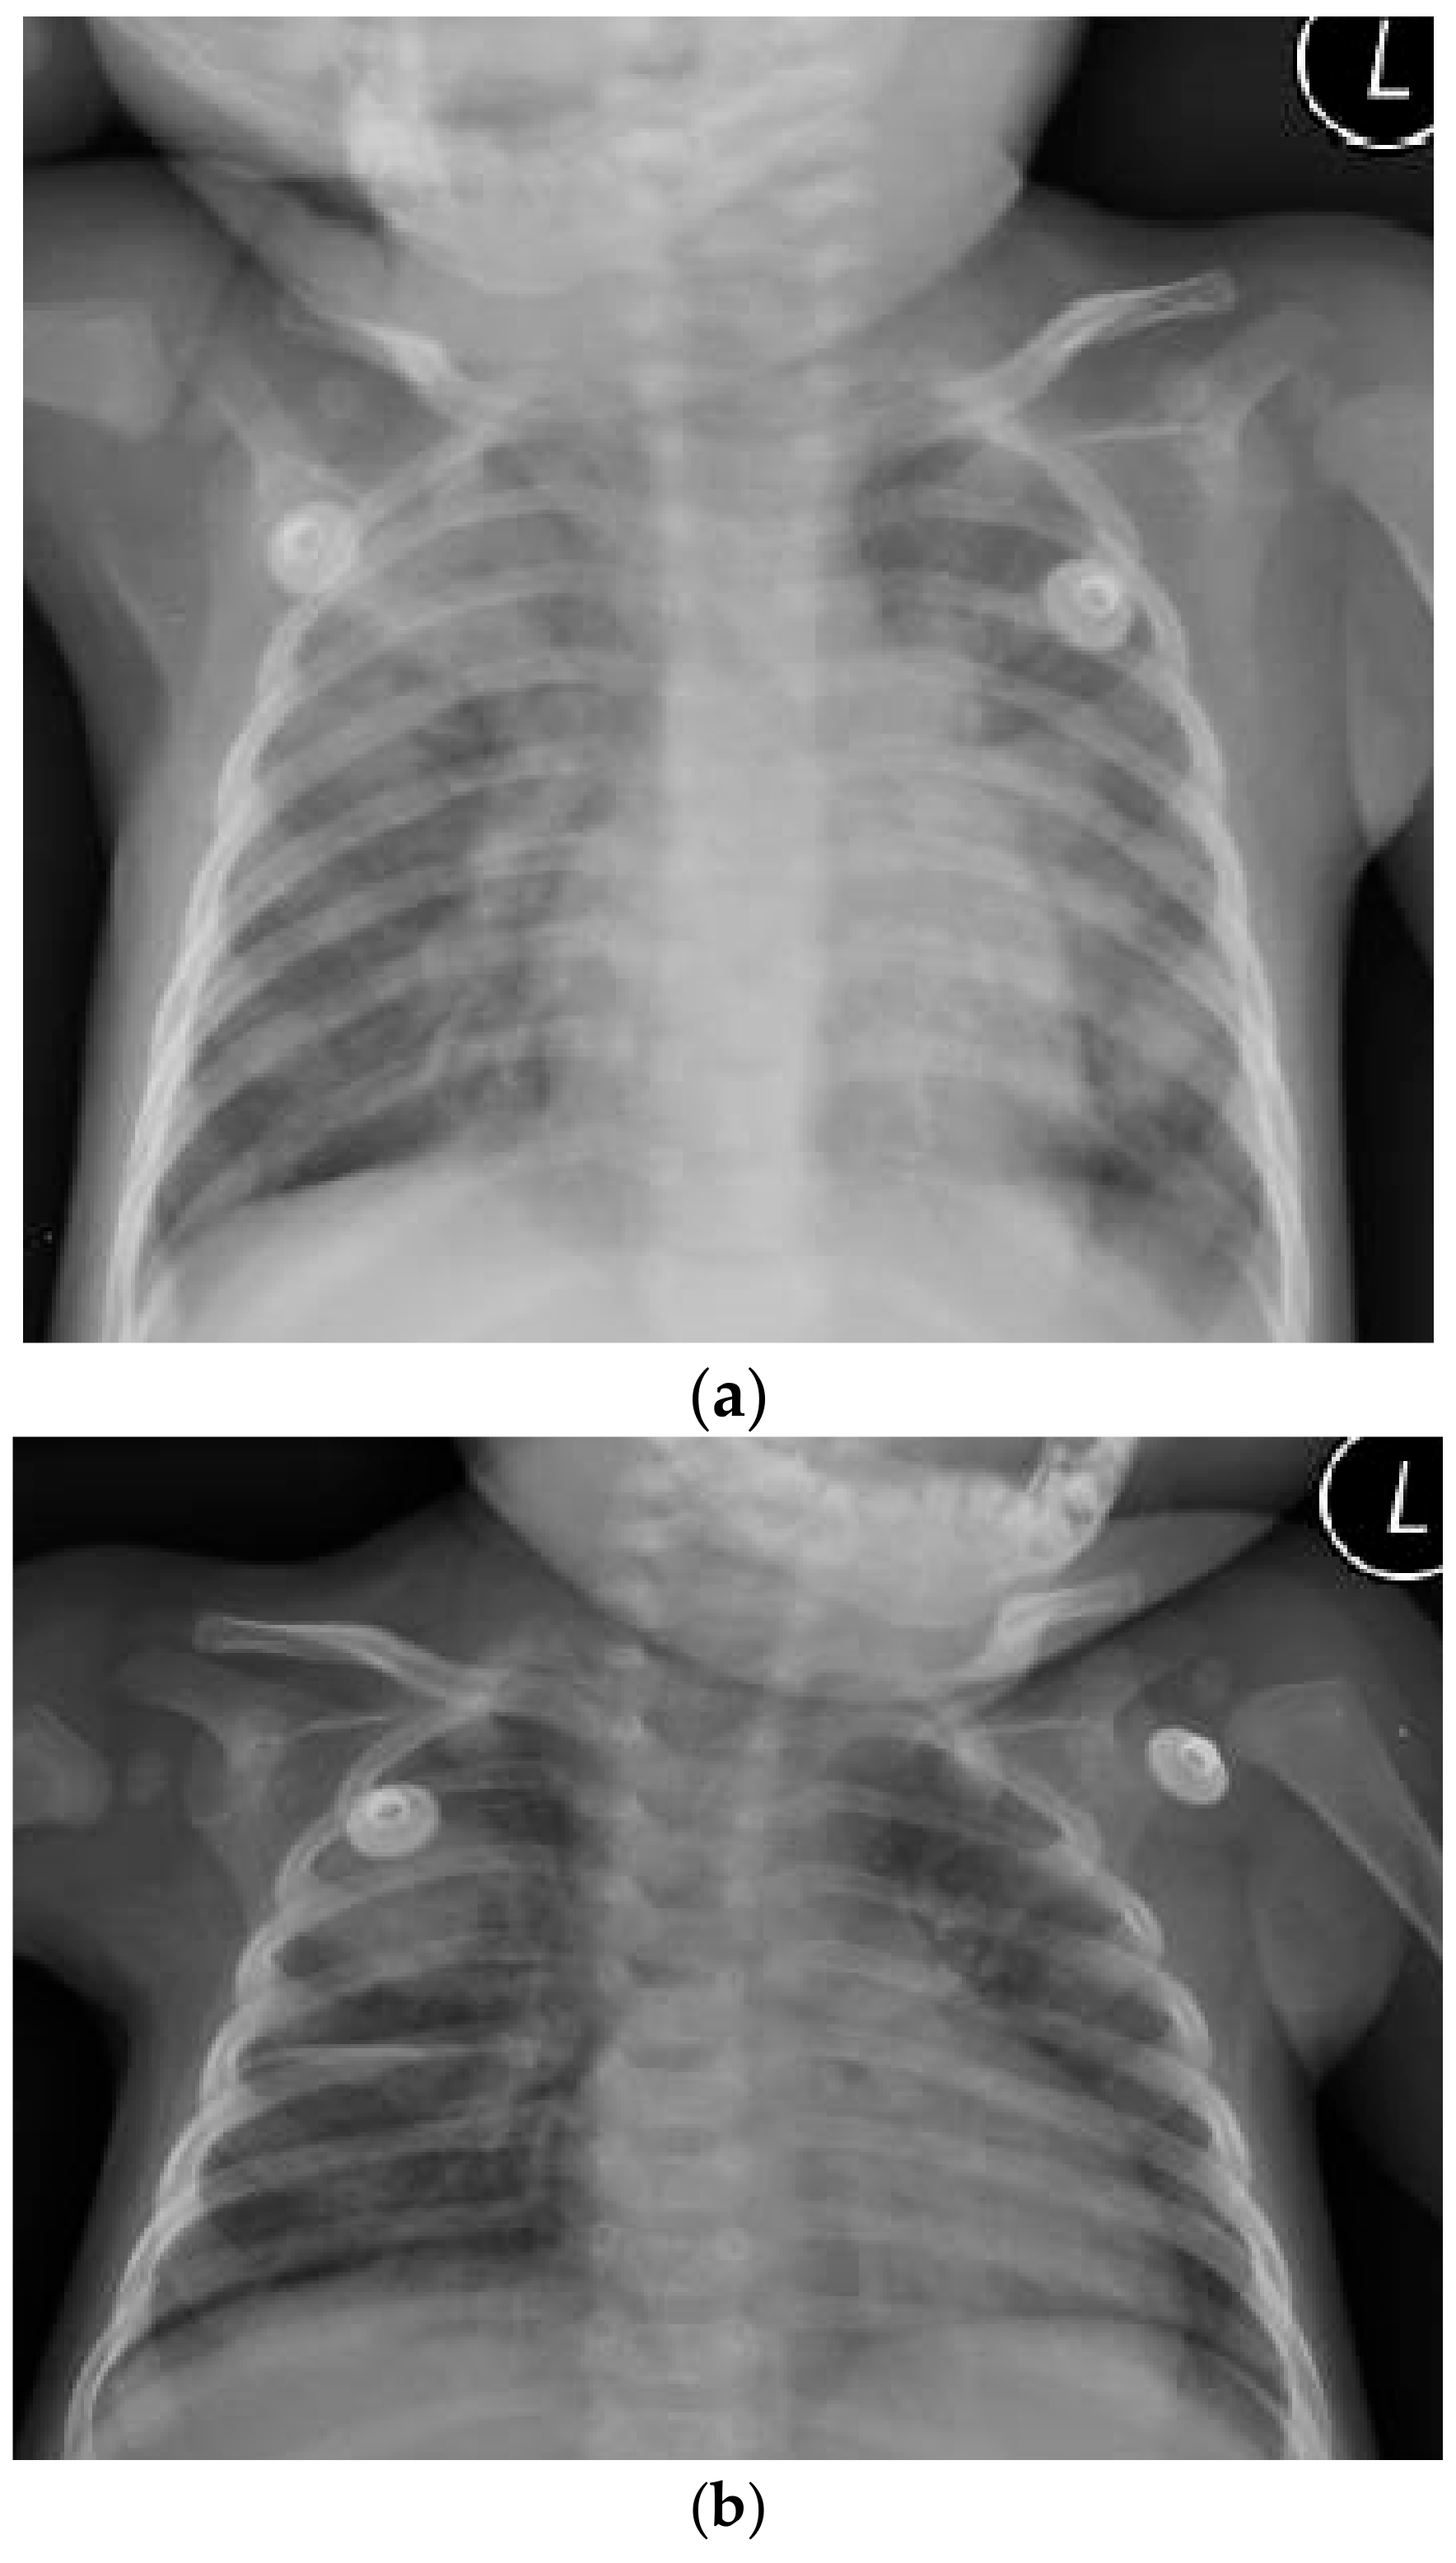

1. Case Report